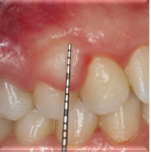

口内检查发现患者13、14牙间牙龈肿胀,质硬,无蒂,牙龈周围轻度菌斑堆积,牙龈轻度红肿。13、14牙不松动。

计划切除增生牙龈。由于增生范围较大,拟利用腭侧牙龈进行软组织修复。